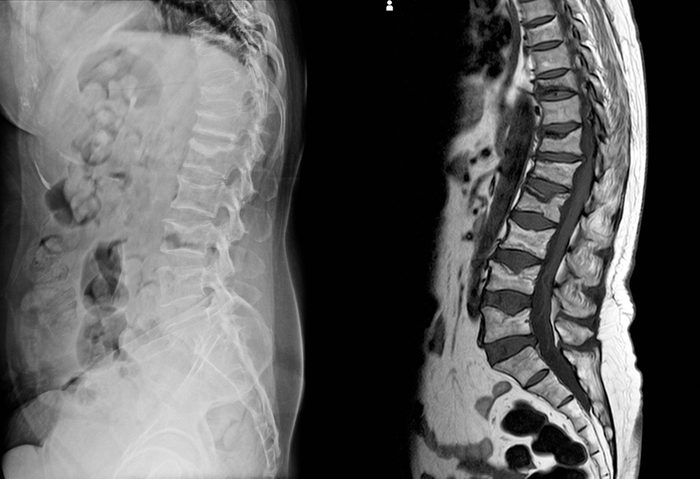

X-ray and MRI Lumbar spine findings severe vertebral collapse of T12 vertebra mild to moderate collapse of L1-2 vertebrae.

You have osteoporosis

If you have known osteoporosis and your back pain comes on suddenly, you could have fractured a vertebrae. “Osteoporotic fractures, also known as insufficiency fractures, are very common in the elderly,” Dr. Anand says. “They may not even feel the break when it happens but the pain becomes debilitating over time.” Common causes could be a recent fall, lifting something heavy, or even a violent cough. (In the meantime, try these exercises that help relieve back pain.)